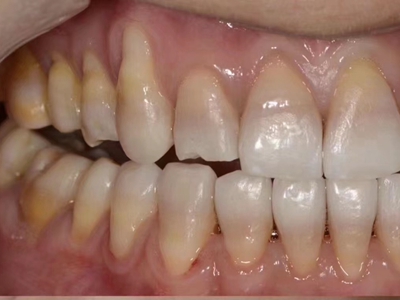

牙龈退缩牙龈萎缩露出牙根图

牙龈退缩发作于上排尖牙和磨牙处,导致牙根暴露在外,伴有牙齿松动、口臭、牙根面敏感等症状,是由于刷牙不当、牙周炎等因素引起。